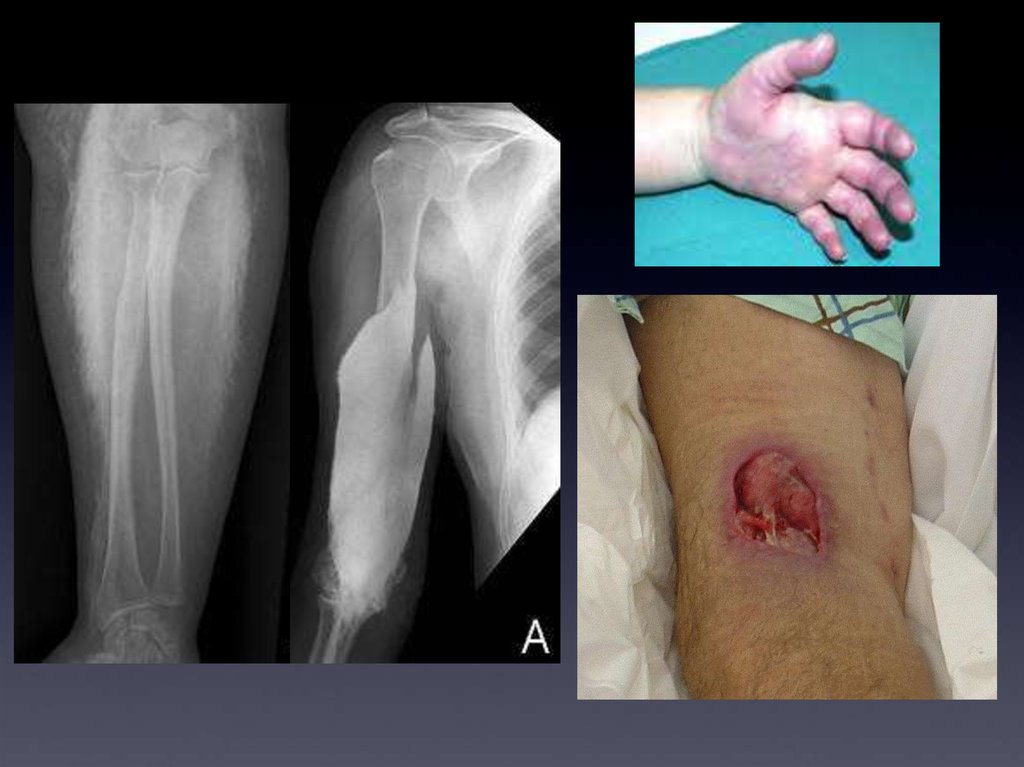

Экстравазация

контрастного вещества

Синдром сдавливания (compartment syndrome), реже

выраженное воспаление мягких тканей и изъязвления

кожных покровов.

Лечение - компрессы на место экстравазации.

Нет точных данных в пользу предпочтения

использования холодных или горячих компрессов.

Tакже нет достоверных данных о эффективности

введения в место экстравазации лекарственных

препаратов (стериоды и т.п.).

Консультация хирурга - при больших объемах.

Пациент должен быть предупрежден о необходимости

обратится к лечащему врачу при проявлениях синдрома

сдавливания (парестезии, etc...) или изьязвлений